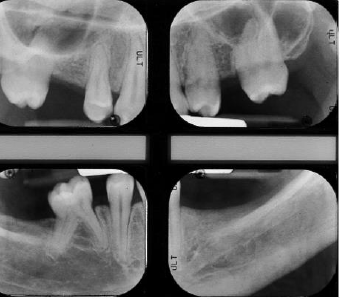

A female patient 28 years old was referred by the orthodontist to complete her dental treatment. Patient presented with several missing teeth due to agenesis, she had only two upper permanent molars and a deciduous one in the lower right side. The request of the patient was to replace two lower molars and one in the upper right side in order to restore proper occlusion (Figures 1-3). As part of the study case the patient was sent for a CBCT in order to evaluate the condition of the edentulous areas (Figure 4) [1].

Unfortunately, the 3D evaluation showed a severe type of horizontal bone resorption in both molar areas, right and left. Priority was given to the lower left side where one bicuspid and all three molars were missing. Nevertheless, the anatomy of the area showed how the combination of horizontal bone loss plus very superficial mandibular canal would allow the placement of one only implant. As part of the planning, stone casts were taken and with the aid of periodontal probes was evaluated the kind of augmentation needed (Figure 5). In order to accommodate a standard diameter implant was requested an augmentation of at least 5-6 mm. It was decided to address this area with the aid of a bone lamina (Cortical Lamina, OsteoBiol by Tecnoss, Coazze, Italy) technique associated with a mix of autogenous bone mixed with collagenated porcine bone graft (GenOs, OsteoBiol by Tecnoss, Coazze, Italy) [2].